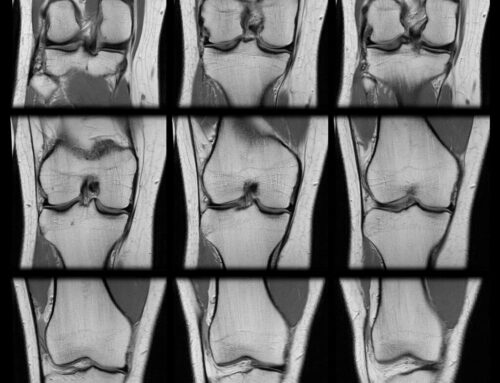

Your orthopedic specialist determines injury severity through physical examination and imaging studies including MRI, which visualizes soft tissue damage and identifies associated injuries to meniscus or other ligaments.